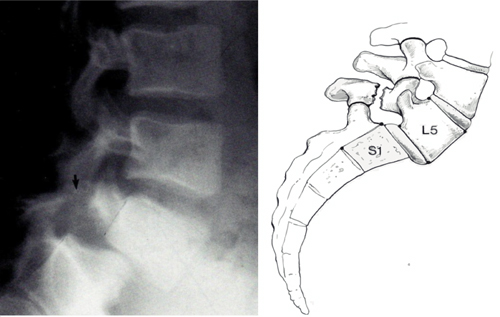

Een spondylolisthesis is een moeilijk woord voor het afglijden van de wervel. Meestal gebeurd dit dus op het onderste niveau, L5-S1. De wervel kan naar "voren" glijden (richting de buik) of naar achteren. Het merendeel betreft een afschuiving naar voren toe. De mate van afschuiving wordt uitgedrukt in een ernstigheidsgraad (van Graad I tot Graad III). Bij graad III (de ergste) is er sprake van een afschuiving van 50%. De af

glijding kan aangeboren zijn, traumatisch plaats vinden of door "ouderdom" (spondylose) komen. De pijnklachten die hierbij horen zijn pijn in de lage rug met eventueel uitstraling naar bijvoorbeeld de hamstring. Meestal heb je de neiging om korte pasjes te maken tijdens het lopen. In veel gevallen hebben mensen echter niet zo veel last van de afglijding. Een spondylolisthesis komt heel veel voor veel bij mensen die hier helemaal geen hinder van ondervinden. In veel gevallen is er dan dus ook geen behandeling nodig.